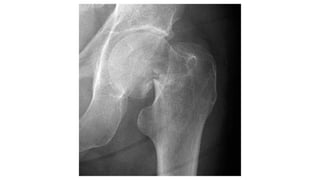

This document discusses femoral fractures, categorized by their location and severity, with classifications such as Garden classification. It outlines the types of fractures, including valgus impacted, non-displaced, partially displaced, and fully displaced, along with their surgical treatment options. Additionally, it briefly describes distal femur fractures, which occur just above the knee joint.